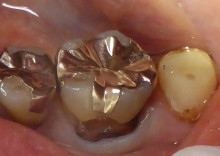

歯の根元に大きな虫歯があります。

虫歯をすべてとると

神経が出てきそうなので、

ドックベスト療法(以前のブログ参照)

を行いました。

そして ダイレクトボンド(以前のブログ参照)

を行います。

当院では できるだけ精密な診療を

行うためにマイクロスコープで

拡大して治療します。

最大 20倍まで拡大できます。

ほとんど歯を削らず治療終了です。